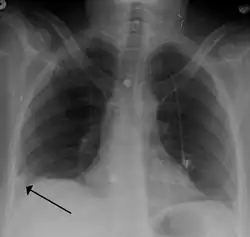

Pulmonary embolism (white arrow) that has been long-standing and has caused a lung infarction (black arrow) seen as a reverse halo sign

- Chest X-rays are often done on people with shortness of breath to help rule out other causes, such as congestive heart failure and rib fracture. Chest X-rays in PE are rarely normal,[70] but usually lack signs that suggest the diagnosis of PE (for example, Westermark sign, Hampton's hump).